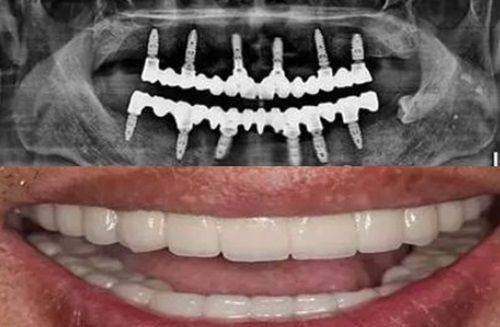

硬件设施:该店数字化设备齐全,采用CBCT三维成像和数字化导板技术,能让种植体定位更精细,创伤更小。

上班族:每晚18:00 - 22:00的夜间专场,种植牙爆款套餐直接降价3000元,矫正、补牙、洗牙还能打8折,既省时间又省钱。有患者分享:“我缺了2颗牙,医生用3D导板种植,手术时间不到1小时,修复也快,3个月就正常吃饭了。”

老年人:对于缺牙的老年人来说,这里的种植技术和服务也特别贴心。有位70岁患者分享:“半口牙缺失,医生做了all - on - 4即刻负重,当天就能戴临时牙,现在吃饭特别香。”